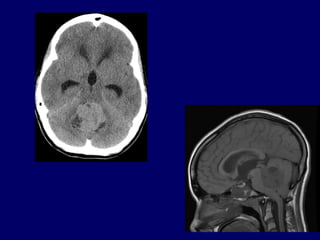

Síndrome do Arquicerebelo

• Ocorre em crianças

• Tumores do IV ventrículo com

compressão do nódulo e pedúnculo do

flóculo, (meduloblastoma)

• Perda do equilíbrio sem alteração do

tônus.

Síndrome do Arquicerebelo •Ocorre em crianças • Tumores do IV ventrículo com compressão do nódulo e pedúnculo do flóculo, (meduloblastoma) • Perda do equilíbrio sem alteração do tônus.